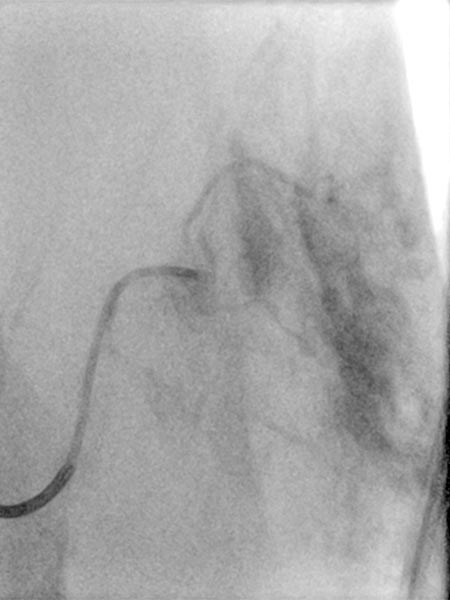

Nachdem am Ende des 3. Lebensjahres immer noch keine Rückbildungstendenz des Tumors sichtbar war, wurde nach einer Biopsie eine Embolisation zur Induktion einer Involution durchgeführt. Die Digitale Subtraktionsangiographie (DSA) zeigt einen Mikrokatheter superselektiv in einem Tumorgefäß. Der Tumor ist stark perfundiert und lobuliert, sehr früher venöser Abstrom, typisch für ein NICH.

Partikelembolisation mit sphärischen Partikeln der Größe 250 Mikrometer über den superselektiv in den Tumor eingeführten Mikrokatheter.